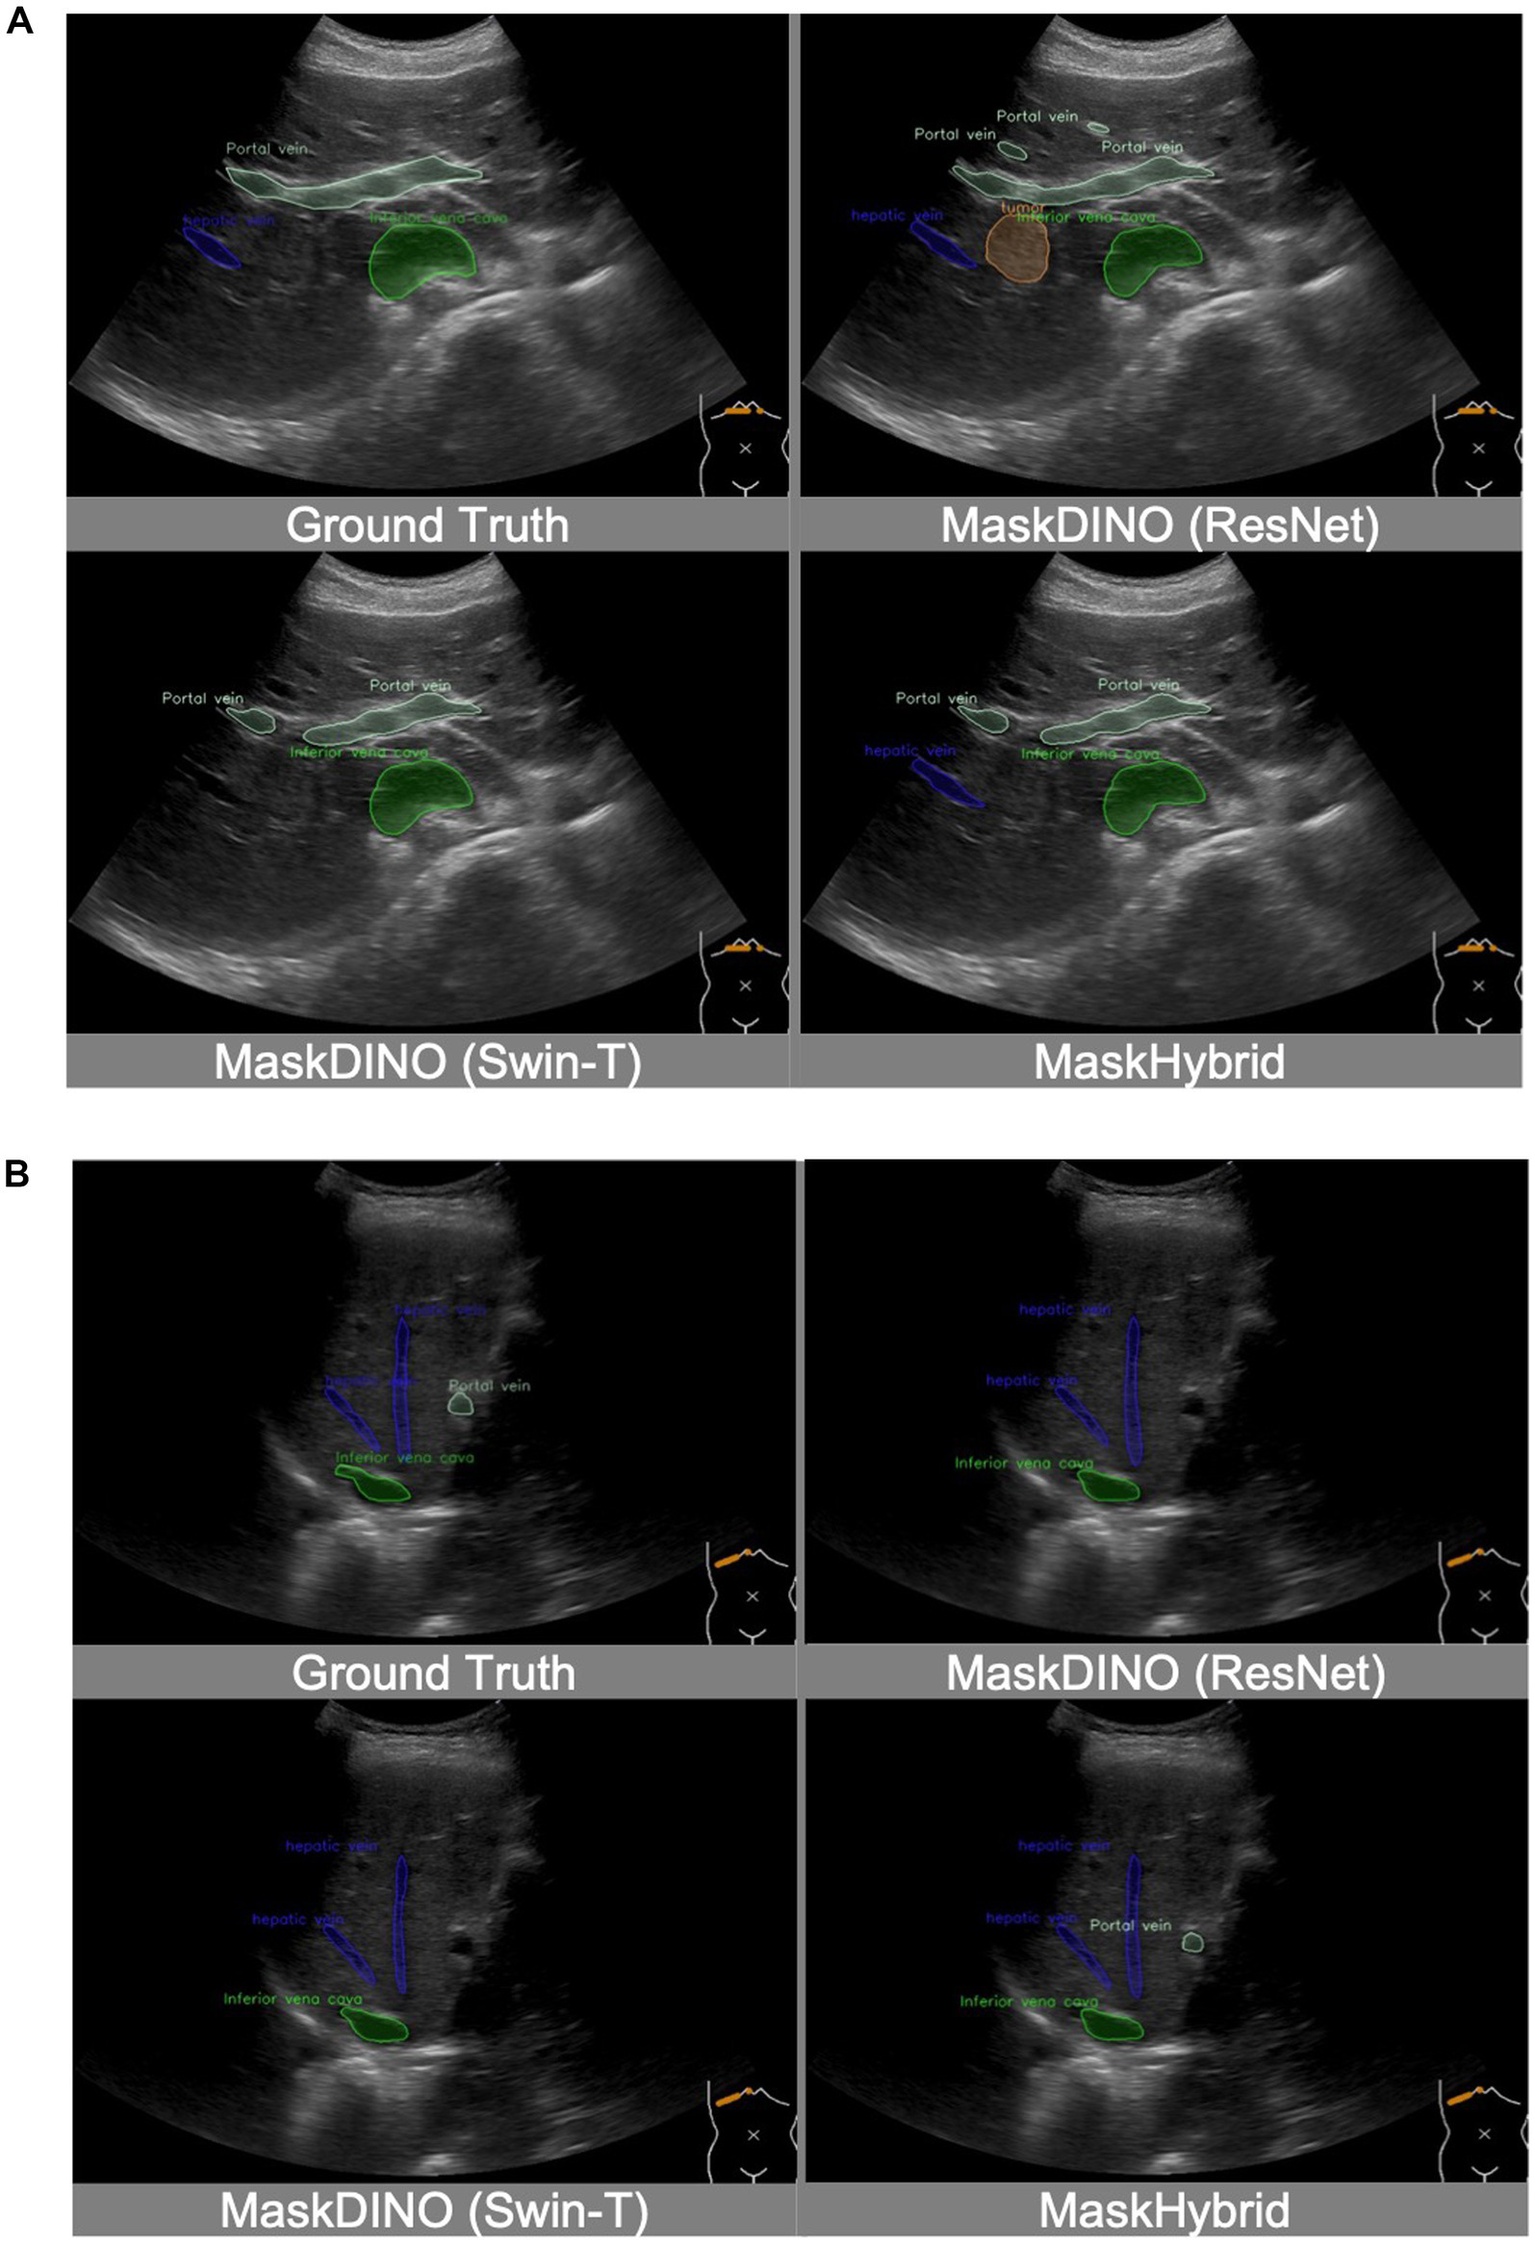

In addition, the MaskHybrid model, incorporating the mamba-transformer hybrid design, achieved the closest visualization effect to the ground truth regarding both annotation type and the number of recognized structures. In contrast, the MaskDINO baselines exhibited missed anatomical structures (hepatic vein in Figure 4A and portal vein in Figure 4B) or the erroneous identification of non-existent lesions (tumor in Figure 4A). However, these structures were correctly recognized in our MaskHybird model. Detailed comparisons between models are provided in the Supplementary Material.

Figure 4

Visualization comparison of baselines and our anatomical recognition model. MaskHybrid achieved the closest visualization effect to the ground truth regarding both annotation type and the number of recognized structures. (A) MaskDINO baselines missed the hepatic vein or the erroneous identification of the tumor. (B) MaskDINO baselines missed the portal vein.